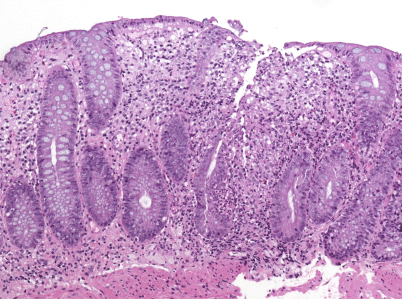

Die histopathologische Diagnose einer chronisch-entzündlichen Darmerkrankung stützt sich auf die Evaluierung von Schleimhautarchitektur und Zellgehalt im Schleimhautstroma [46]. Sowohl eine gestörte Kryptenarchitektur als auch metaplastische Veränderungen, wie z.B. die Panethzellmetaplasie im linken Kolon (bei Colitis ulcerosa) oder die Pylorusdrüsenmetaplasie im terminalen Ileum (bei Morbus Crohn), weisen auf chronische Prozesse hin. Der Zellgehalt im Stroma ist erhöht, kontinuierlich bzw. diffus bei (unbehandelter) Colitis ulcerosa (Abb. 1), diskontinuierlich bei Morbus Crohn (Abb. 2). Neutrophile Granulozyten, im Stroma wie im Epithel (Kryptitis, Kryptenabszesse), sind ein Anzeichen für eine entzündliche Aktivität, ebenso Erosionen und Ulzera.

Abb. 1

Colitis ulcerosa mit schwerer Kryptenarchitekturstörung und kontinuierlicher chronisch-aktiver Entzündung